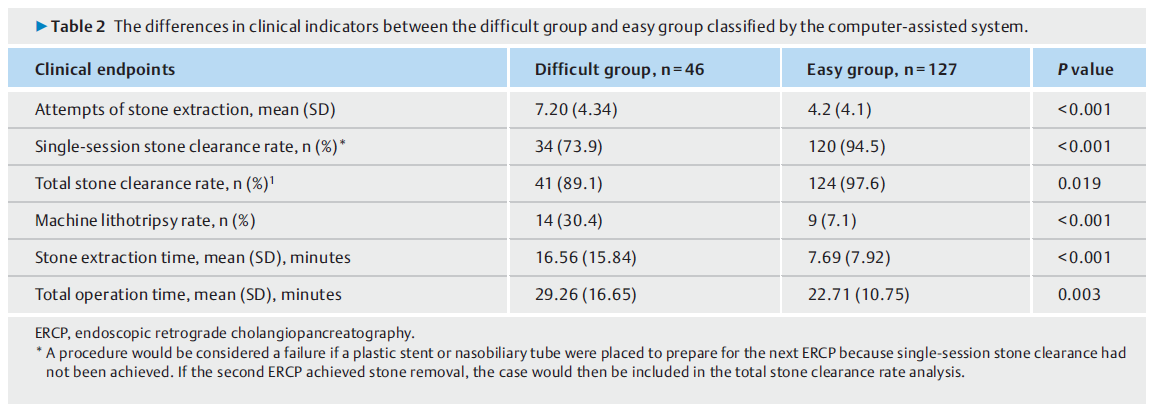

来自三家医院的173例CBD结石患者被纳入研究。与CAD分为容易组相比,CAD分为困难组的取石尝试次数更多(7.20比4.20,P<0.001),机器碎石次数更多(30.4%比7.1%,P<0.001),取石时间更长(16.59比7.69分钟,P<0.001),单次取石率较低(73.9%比94.5%,P<0.001),总取石率较低(89.1%比97.6%,P=0.019)。

与简单组相比,困难组需要多尝试三次(95 %CI 1.58-4.40; P < 0.001)和更频繁的机器碎石(30.4 % vs. 7.1 %; P < 0.001)才能清除结石。困难组和简单组的单次结石清除率分别为73.9%和94.5%,总结石清除率分别为89.1%和97.6%。结石清除失败的病例主要是由于结石尺寸较大和远端 CBD 臂较短所致。有四名患者因结石充满 CBD 而无法清除结石。另有两例患者因年老无法忍受长时间麻醉而放弃取石。困难组的取石时间(16.59vs.7.69 min;P<0.001)和总手术时间(29.26 vs.22.71 min;P=0.003)分别显著高于容易组。(表2)总结了两组临床特征的统计比较。

表2. 计算机辅助系统分类困难组与容易组临床指标的差异。